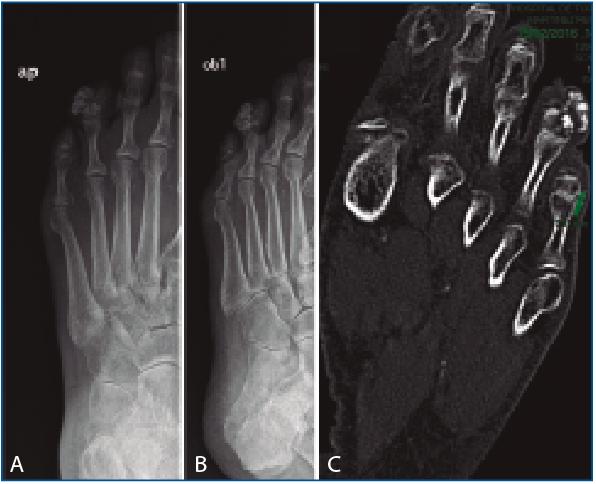

En la exploración física se evidenció una tumoración a nivel lateral de la falange distal del 4.º dedo del pie izquierdo. En la radiografía de pie, se observó una masa con matriz cartilaginosa en el margen lateral del 4.º dedo del pie izquierdo de características benignas (Figuras 1A y 1B). Se completó el estudio con una tomografía computarizada de pie izquierdo donde, además de la lesión descrita anteriormente, se visualizó una tumoración de similares características en el margen lateral del 5.º dedo, junto a la articulación interfalángica proximal, de aproximadamente 7 mm (Figura 1C).

Figura 1. A: radiografía anteroposterior de pie izquierdo, donde se aprecia en el margen lateral del 4.º dedo una masa calcificada; B: radiografía oblicua de pie izquierdo, donde se evidencia en el margen lateral del 4.º dedo una masa con matriz cartilaginosa; C: tomografía computarizada en la que se observa una tumoración con matriz cartilaginosa en el margen lateral del 4.º dedo, junto a la articulación interfalángica distal, de 12 × 11 mm, de aspecto grumoso, que parece depender de la cortical ósea. También se aprecia otra tumoración de similares características en el margen lateral del 5.º dedo, junto a la articulación interfalángica proximal, de aproximadamente 7 mm.